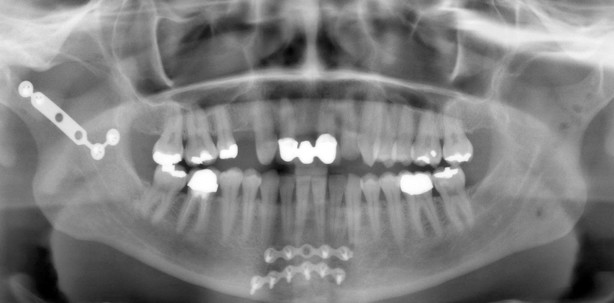

Die Patientin ist seit April 2002 in regelmäßiger Behandlung in unserer Praxis. Nach jährlicher Kontrolle stellte sie sich am 21.11.2005 nach operativer Versorgung multipler Frakturen im Ober- und Unterkiefer vor. Aufgrund eines Fahrradsturzes am 04.10.2005 erlitt die Patientin folgende Verletzungen: tiefe dislozierte Collumfraktur beidseits, Trümmerfraktur im Corpus mandibulae Regio 31/41, Alveolarfortsatzfraktur Regio 14–22, Avulsion von Zahn 11, Luxation der Zähne 21,12,13 und 14, Zahnfrakturen an den Zähnen 14,13,12,21, 22 und zahlreiche Weichteilverletzungen (Abb. 1). Am 05.10.2005 erfolgten die Reposition der Alveolarfortsatzfraktur sowie das Einbinden von Kieferbruchschienen mit Drahtligaturen. Am 07.10.2005 wurde die Reposition und Plattenosteosyn these im Bereich des Unterkiefers durchgeführt. Die Versorgung der Fraktur des rechten Collums erfolgte mittels Titanplatte, während die Fraktur des linken Collums mit einer resorbierbaren Platte versorgt wurde. Die Trümmerfraktur im Bereich des Corpus mandibulae wurde ebenfalls mit zwei Titanplatten fixiert. Die starre mandibulo-maxilläre Verschnürung wurde am 14.10.2005 gelöst und die Fixierung erfolgte von da an mit Gummizügen, bis sie am 18.10.2005 vollständig entfernt wurde. Das Anliegen der Patientin war nun die Wiederherstellung der Funktionen des orofazialen Systems. Die Patientin war zu diesem Zeitpunkt im dritten Monat schwanger.

Es ergibt sich folgender intraoraler Befund vom 21.11.2005 (Abb. 2): Die Zähne 14 und 11 fehlen, die Zähne 13 und 12 weisen eine Ellis 1-, die Zähne 21 und 22 eine Ellis 2-Fraktur auf. Alle Zähne wurden hinsichtlich der Vitalität getestet, bei 17, 13, 12, 21, 27, 33, 42, 43, 47 ist die Vitalitätsprobe negativ. Es imponieren ein frontal offener Biss von 15–25 und eine Mittellinienverschiebung von 4 mm nach links. Ein Abbeißen im Frontzahnbereich ist nicht möglich. Die Unterkieferfrontzähne sind retroinkliniert, die Zähne 31 und 41 sind intrudiert und es liegt ein frontaler Engstand im Unterkiefer vor. Es ergibt sich folgender FRS-Röntgenbefund: neutralbasale Kieferrelation, posteriore Inklination der Mandibula, vertikaler Wachstumstyp.